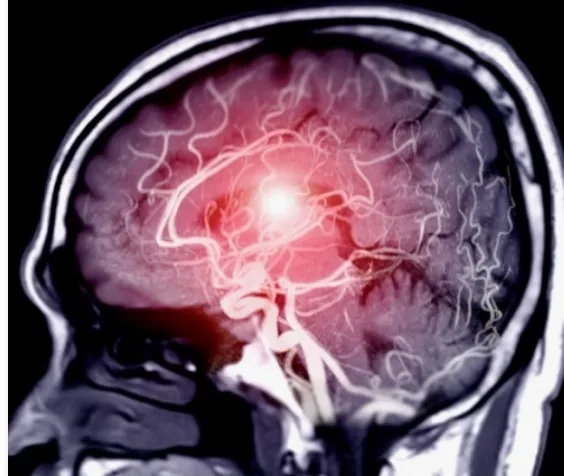

그때까진 뇌 검사를 해본 적이 없었는데, 우연히 검사 항목이 바뀌어 처음으로 뇌를 촬영하게 되었다.

결과는 뜻밖이었다.

정상적인 뇌는 양쪽이 모두 선명히 보이지만, 내 뇌는 한쪽만 뚜렷했고 다른 한쪽은 새까맣게 보이지 않았다.

뇌로 가는 혈관이 한쪽에서만 공급되고, 다른 한쪽은 막혀 있다는 것이다.

그 길로 나는 입원해 [뇌혈관 조영술]을 받게 되었다.

대퇴부 혈관을 통해 카테터를 넣어 뇌 속 혈류의 흐름을 보는 시술이었다.

결과는 분명했다.

내 한쪽 뇌의 굵은 혈관은 완전히 막혀 있었고, 대신 여러 개의 가늘고 얇은 혈관들이 비정상적으로 우회하며 혈류를 운반하고 있었다.

주치의는 그것을 '고속도로 대신 국도로 달리는 피'라고 표현했다.

만약 그 국도 중 하나라도 막혔다면, 나는 이 세상 사람이 아니었을지도 모른다고 했다.